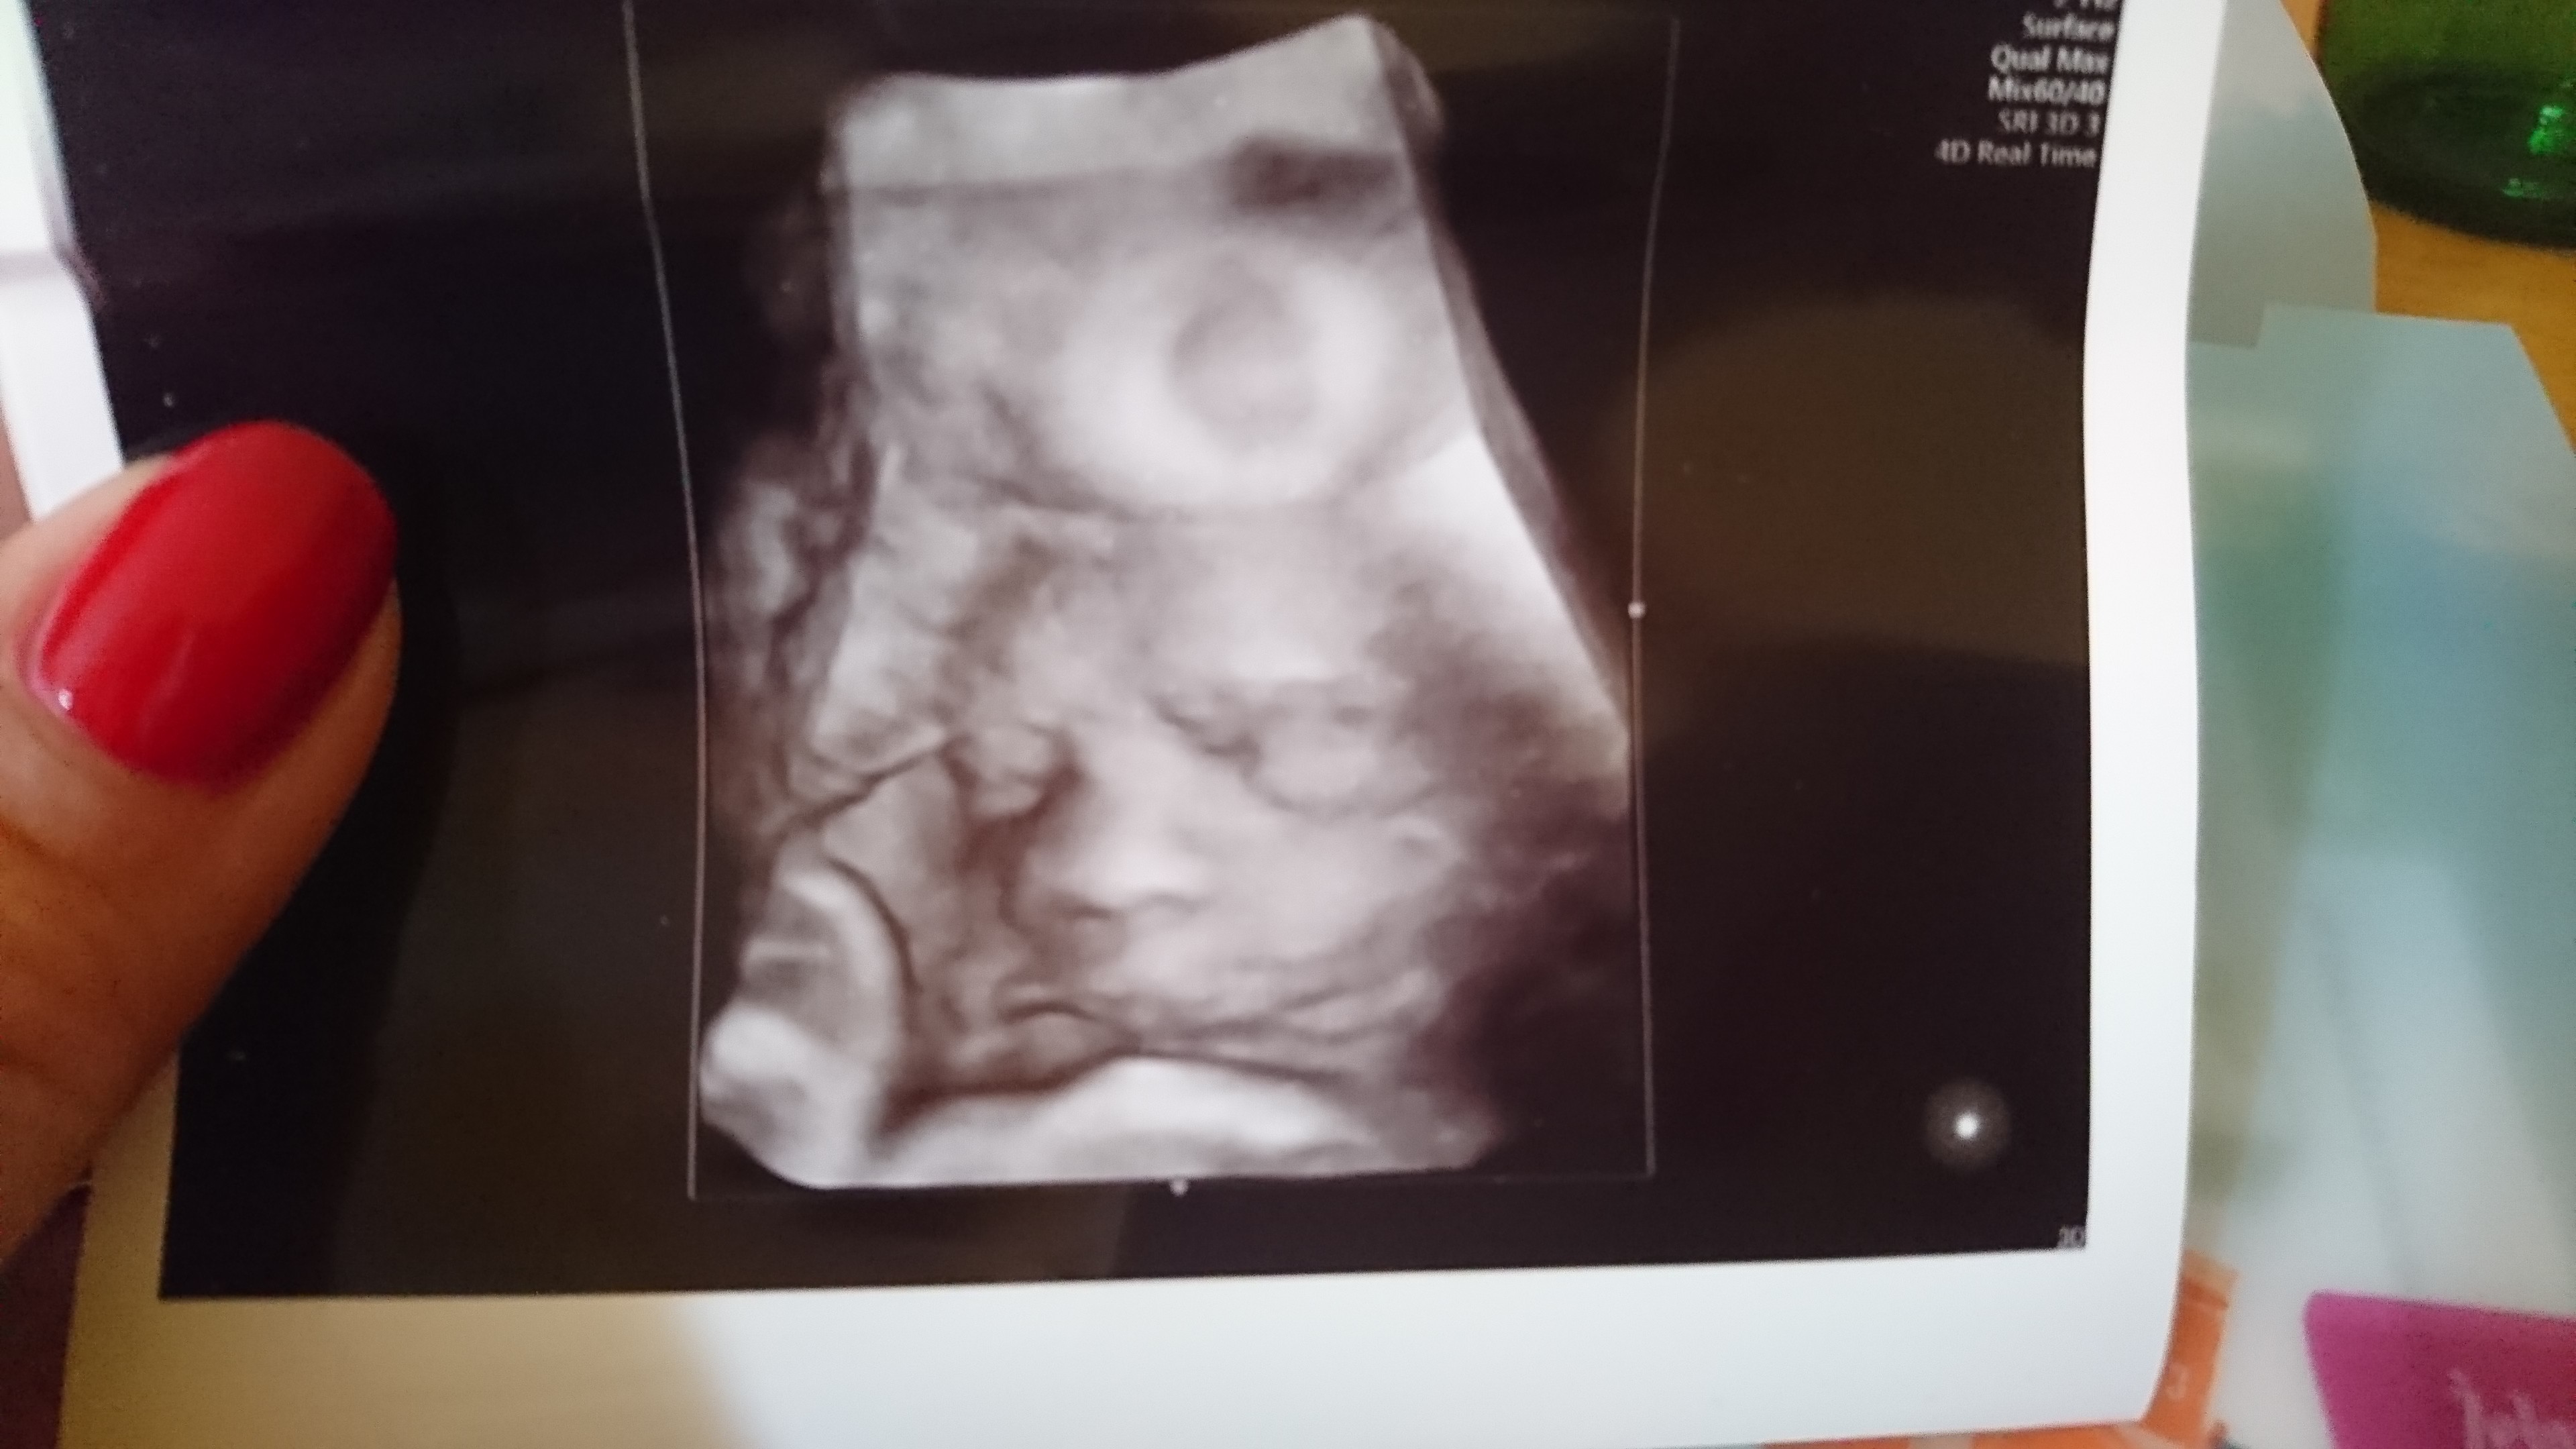

Później was Doczytam jako lektura do łóżka, już po wizycie dziś jestem zadowolona mały ma się dobrze nawet widziałam jak otwiera usta, rośnie jak na drożdżach jest o dwa tyg większy niż powinien,ułożony posladkowo, szyjka długa,zapas heparyny mam, pytałam o ten acard powiedział że mam brać do 35tc i to że w ulotce jest napisane że nie można w trzecim trymestrze to obalil mit powiedział że on kieruje się nowoczesnym leczeniem udowodnionymi badaniami i jest pewien że w moim przypadku te tabletki pomagają a nie szkodzą, może wam się też przyda ta wiedza ale zapytałam go o pepowine czy lekarz widzi na usg czy dziecko jest owiniete pepowina powiedział że widzą i że do dwóch razy owiniecia nie mówią pacjentce dopiero przy trzecim razie informują i obserwują, uspokoił mnie ze w razie czego on jest od tego aby to dostrzec i odpowiednio poprowadzić ciaze, poinformowałalam swojego również o mojej poprzedniej ciężkiej cesarce że zostałam zarażona gronkowcem i że o mały włos nie dostałam zapalenia otrzewnej w sumie dobrze wyszło że to powiedziałam bo zachowa odpowiednie leczenie po cesarce dostanę od razu antybiotyk itp oraz zapewnił mnie ze z jego strony całe rozwiązanie ciąży odbędzie się pod jego kontrola i że tak jak sobie życzę zostanę porządnie zszyta i wyczyszczona - dzisiejsza wizyta bardzo mnie uspokoiła, heparyne będę brać nawet do 6tyg po cesarce, później wyślę wam fotkę małego..... Ktoś pytał o prenatalne ja robię właśnie za niecały miesiąc u swojego lekarza 45min szczegółowe usg do tego jak się uda fajne zdjęcia 3d cena 250zl

Zapas heparyny i Damianek

Załączniki

• DSC_2029.JPG

DSC_2029.JPG

876,5 KB · Wyświetleń: 136